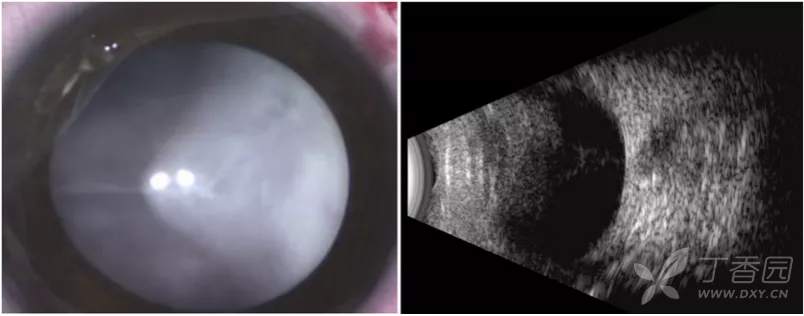

图. 5B期:由于纤维血管组织,视盘不可见。

图. 5B期:外部照片眼前节正常,由于晶状体后纤维血管组织形成,视盘或视网膜不可见。B超显示完全性视网膜脱离,呈后部闭合漏斗状结构。